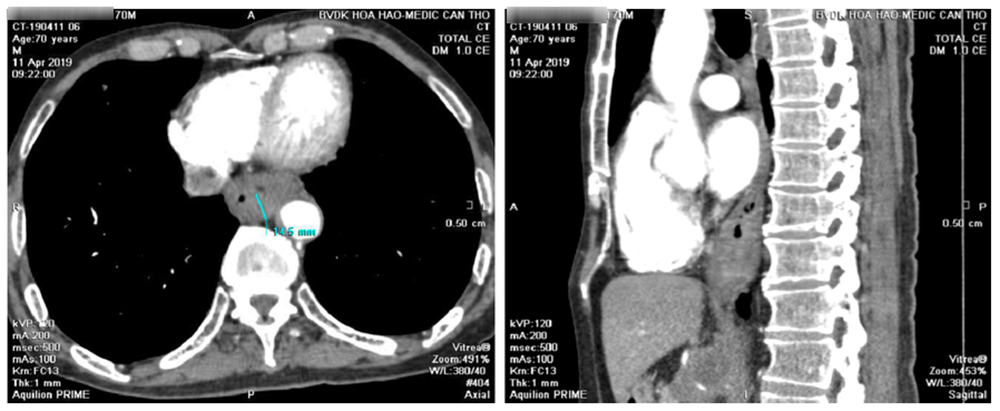

Msct toàn thân có tiêm thuốc cản quang

Dầy thành thực quản 15mm kéo dài 1/3 cuối thực quản, bắt thuốc cản quang mạnh, chùm hạch lớn vùng đầu tụy 5cm